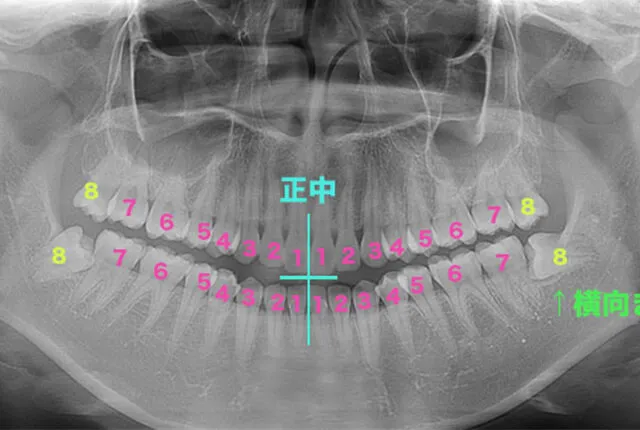

親知らずとは、正中から数えて8番目の歯のことです。「第三大臼歯」や「智歯(ちし)」とも呼ばれ、多くの場合10代後半から20代前半にかけて生えてきます。

人間の歯は、正中(中心)から1番・2番・3番と番号がついており、8番まであります。この8番目の歯が親知らずです。